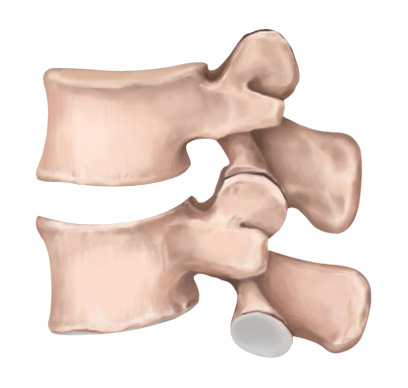

STEP 01

손상된 디스크

STEP 02

손상된 디스크 제거